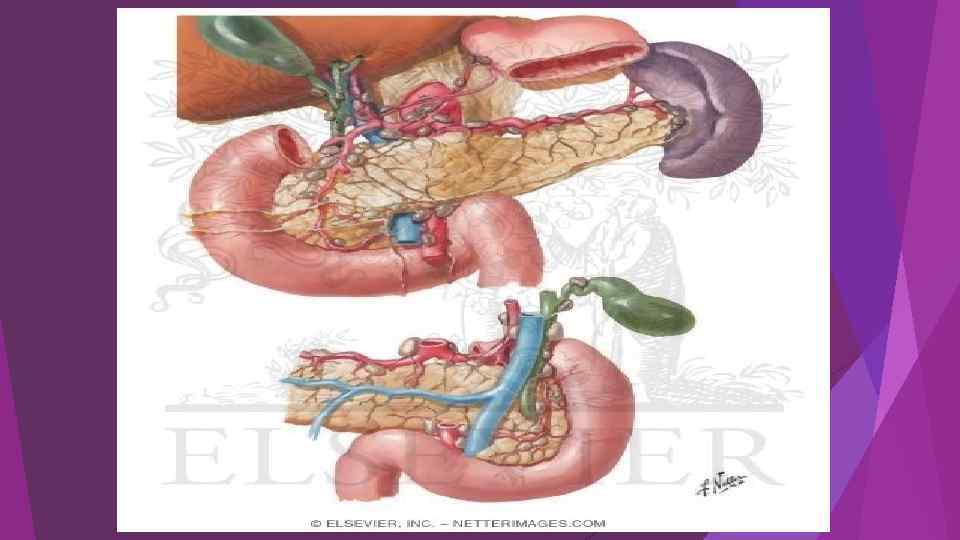

Методы дренирующих операций забрюшинного пространства и брюшной полости при панкреонекрозе "Закрытый" метод дренирующих операций - активное дренирование забрюшинной клетчатки и брюшной полости в условиях анатомической целостности полости сальниковой сумки и брюшной полости. Установка многоканальных дренажей для введения антисептических растворов в очаг деструкции с постоянной активной аспирацией. Контроль за очагом деструкции и функцией дренажей осуществляется по результатам УЗИ, КТ, видеооптической техники, фистулографии. Применяют методы эндоскопического дренирования и санации забрюшинного пространства через поясничный внебрюшинный доступы. Все большее распространение получают малоинвазивные хирургические методы чрескожного пункционного дренирования парапанкреатической зоны и других отделов забрюшинной клетчатки, желчного пузыря под контролем УЗИ и КТ. Малоинвазивные вмешательства легко выполнимы, малотравматичны и эффективны при обоснованном показании и соблюдении методологии. При неэффективности вышеперечисленных методов дренирования при панкреонекрозе показана лапаротомия.

Методы дренирующих операций забрюшинного пространства и брюшной полости при панкреонекрозе "Закрытый" метод дренирующих операций - активное дренирование забрюшинной клетчатки и брюшной полости в условиях анатомической целостности полости сальниковой сумки и брюшной полости. Установка многоканальных дренажей для введения антисептических растворов в очаг деструкции с постоянной активной аспирацией. Контроль за очагом деструкции и функцией дренажей осуществляется по результатам УЗИ, КТ, видеооптической техники, фистулографии. Применяют методы эндоскопического дренирования и санации забрюшинного пространства через поясничный внебрюшинный доступы. Все большее распространение получают малоинвазивные хирургические методы чрескожного пункционного дренирования парапанкреатической зоны и других отделов забрюшинной клетчатки, желчного пузыря под контролем УЗИ и КТ. Малоинвазивные вмешательства легко выполнимы, малотравматичны и эффективны при обоснованном показании и соблюдении методологии. При неэффективности вышеперечисленных методов дренирования при панкреонекрозе показана лапаротомия.

Открытый метод дренирующих операций Основными показаниями к "открытому" методу дренирования забрюшинного пространства являются: - крупномасштабные формы панкреонекроза в сочетании с поражением забрюшинной клетчатки; - инфицированный панкреонекроз и панкреатогенный абсцесс в сочетании с крупноочаговыми формами инфицированного панкреонекроза; - релапаротомия после неэффективного "закрытого" или "полуоткрытого" методов дренирования. Основные варианты технических решений, определяемых распространенностью и характером поражения забрюшинного пространства и брюшной полости: - панкреатооментобурсостомию + люмботомию (+ лапаростомию) и дренированием всех зон некроза дренажами Пенроза в комбинации с многопросветными трубчатыми конструкциями Выполнение адекватных некрсеквестрэктомий проводятся в программируемом режиме с интервалом 48 -72 ч. Полуоткрытый метод дренирования установка трубчатых многопросветных дренажных конструкций в комбинации с дренажем Пенроза. В этих условиях лапаротомную рану ушивают послойно, а комбинированную конструкцию дренажей выводят через широкую контрапертуру в пояснично-боковых отделах живота (люмботомия). смена дренажных конструкций отсрочена на 5 -7 сут.

Открытый метод дренирующих операций Основными показаниями к "открытому" методу дренирования забрюшинного пространства являются: - крупномасштабные формы панкреонекроза в сочетании с поражением забрюшинной клетчатки; - инфицированный панкреонекроз и панкреатогенный абсцесс в сочетании с крупноочаговыми формами инфицированного панкреонекроза; - релапаротомия после неэффективного "закрытого" или "полуоткрытого" методов дренирования. Основные варианты технических решений, определяемых распространенностью и характером поражения забрюшинного пространства и брюшной полости: - панкреатооментобурсостомию + люмботомию (+ лапаростомию) и дренированием всех зон некроза дренажами Пенроза в комбинации с многопросветными трубчатыми конструкциями Выполнение адекватных некрсеквестрэктомий проводятся в программируемом режиме с интервалом 48 -72 ч. Полуоткрытый метод дренирования установка трубчатых многопросветных дренажных конструкций в комбинации с дренажем Пенроза. В этих условиях лапаротомную рану ушивают послойно, а комбинированную конструкцию дренажей выводят через широкую контрапертуру в пояснично-боковых отделах живота (люмботомия). смена дренажных конструкций отсрочена на 5 -7 сут.